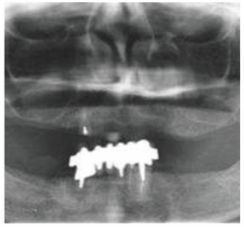

種牙前X光片

種植修復后X光片

這一位老先生則選擇了All-on-4種植技術,即拔即種,上下頜分別種植4個植體就完成了全口牙齒修復,費用降低了不少,而且創(chuàng)傷小,恢復快。